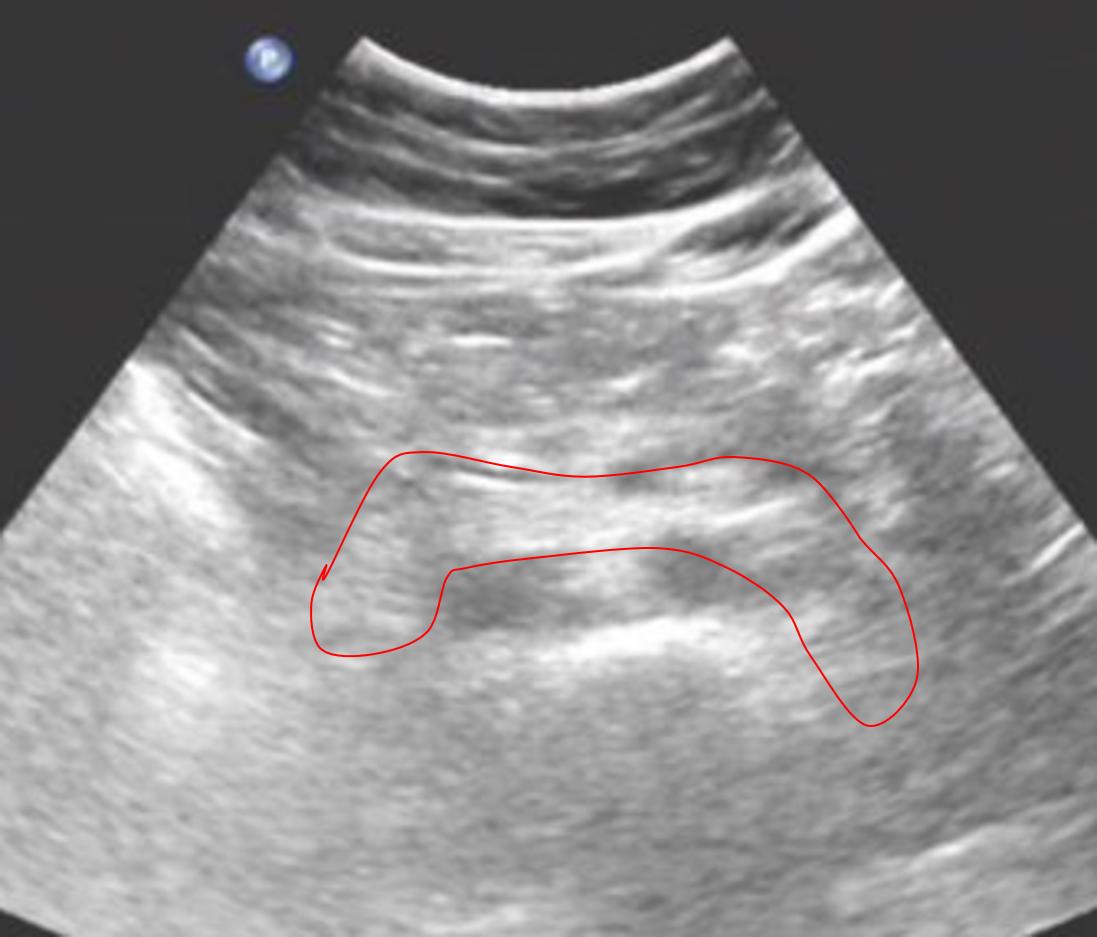

图二,空腹的患者,红线圈出来的部分就是胰腺,可以看到这个胰腺回声均匀,并且没有长东西,是一个健康的胰腺~

对于一些餐后的患者,就无法检查到胰腺炎以及一些占位性病变了(指的就是胰腺癌啊,胰腺的囊肿啊等等,尤其是胰腺炎,晚上值急诊班的时候,有部分腹痛的患者,胰腺炎的症状很明显,但是彩超看不到,就是因为大多数吃完晚饭,胃里还有很多食物残渣和气体,影响了超声的检查效果),这也是一些彩超报告中所谓的“上腹积气,胰腺无法扫查”,不是大夫不给好好看,是真的看不到啊……